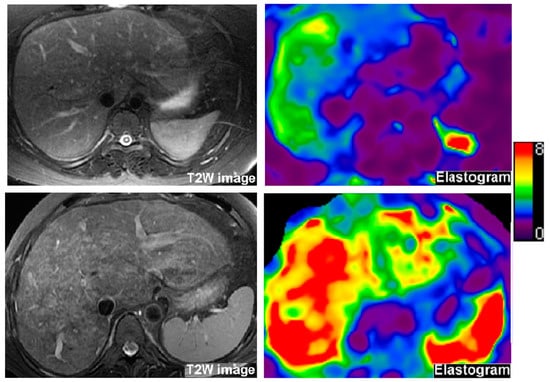

2.3. Liver MRE